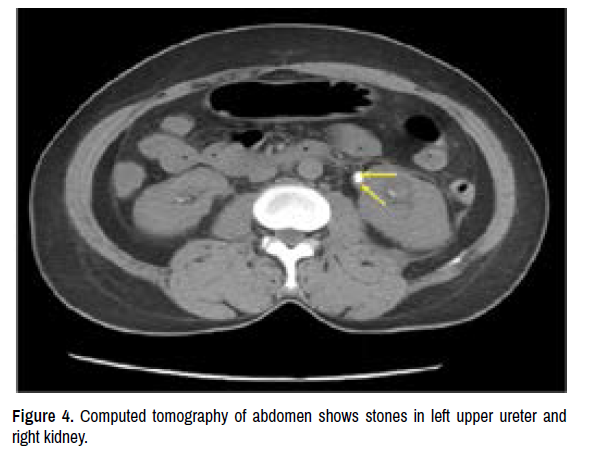

A 48-year-old woman complained of backache, fever, short of breath accompanying skin mottling was admitted to the ICU presenting septic shock. The laboratory tests showed severe coagulation dysfunction, metabolic acidosis and unstable hemodynamic. The whole abdominal CT scan showed there were stones in left upper ureter and right kidney (Figures 2-4). The patient was intubated and ventilated immediately due to shortness of breath. We started high-dose NE because of refractory hypotension. Broad-spectrum antibiotics, fluid resuscitation, and continuous renal replacement therapy were all initialed to rescue the patient. As shown in Table 1, the coagulation profile of patient suggested Disseminated Intravascular Coagulation (DIC). The high dose NE treatment (average dose 1.24 μg/kg/min) was maintained for 69 hours, and the fingers and toes appeared ischemic necrosis (Figures 5 and 6) at the tenth day even we decreased the dose of NE. We performed bedside ultrasonography to find the possible causes; however, these examinations did not reveal any diagnostic clues. Unfortunately, we were unable to perform more invasive evaluations (e.g., angiography), due to the patient’s poor general condition. We elevated the extremity in attempt to minimize local edema, keeping the extremity warm and applying topical nitroglycerin, but which had very little effect. The patient was successfully weaned off and transferred to the general ward one month later. However, she was readmitted to the ICU again due to repeating infection, and died three weeks later.

Figure 4. Computed tomography of abdomen shows stones in left upper ureter and right kidney.